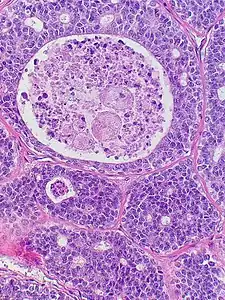

| Micrograph of an adenoid cystic carcinoma of a salivary gland (right of image): Normal serous glands, typical of the parotid gland, are also seen (left of image), H&E stain. | |

Histopathological image of adenoid cystic carcinoma of the salivary gland infiltrating a nerve (center), H&E stain